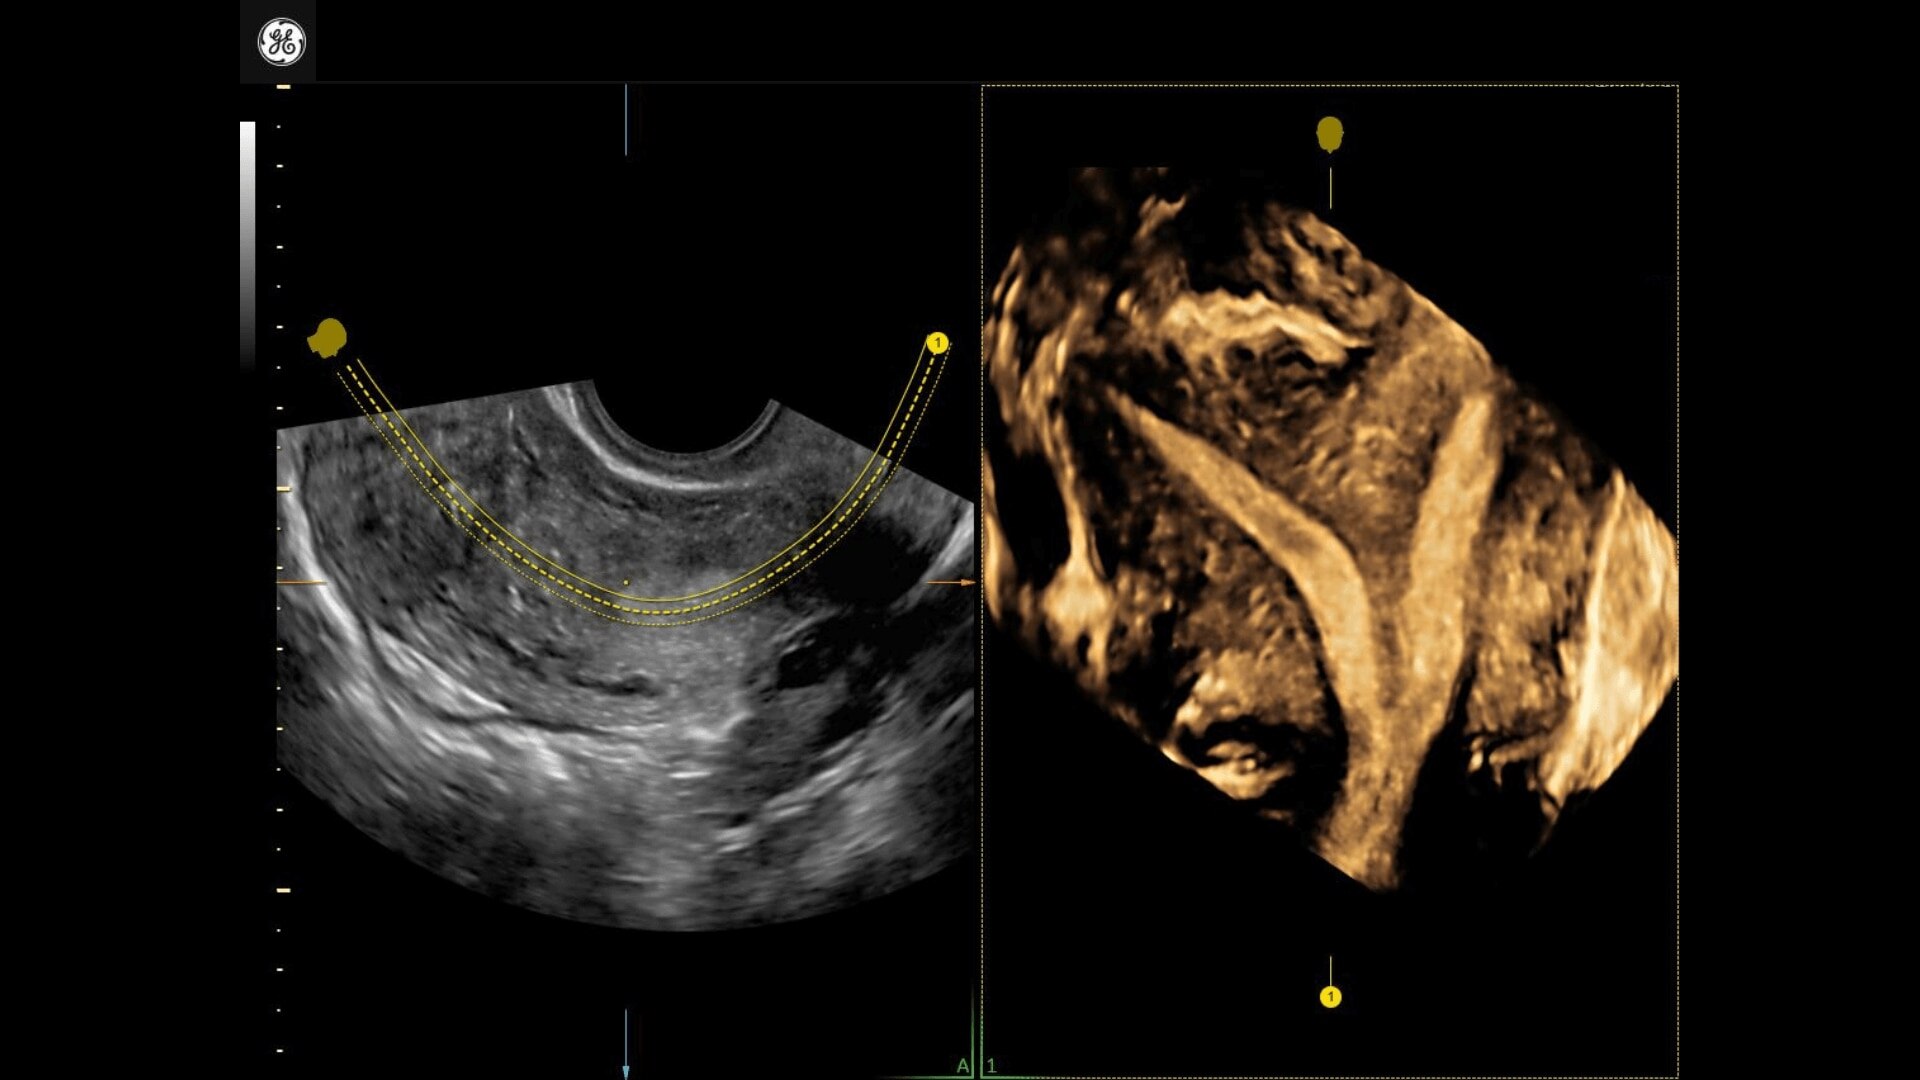

Uterine Trace

Easy display coronal view of uterus.

• Uterine Trace acquires the volume & then displays the coronal view of the uterus to simplify identification & reporting of uterine malformations.

• Uterine Trace acquires the volume and then displays the coronal view of the uterus linking to ASRM, ESHRE and ESGE Uterine Classification guidelines to simplify identification and reporting of uterine malformations